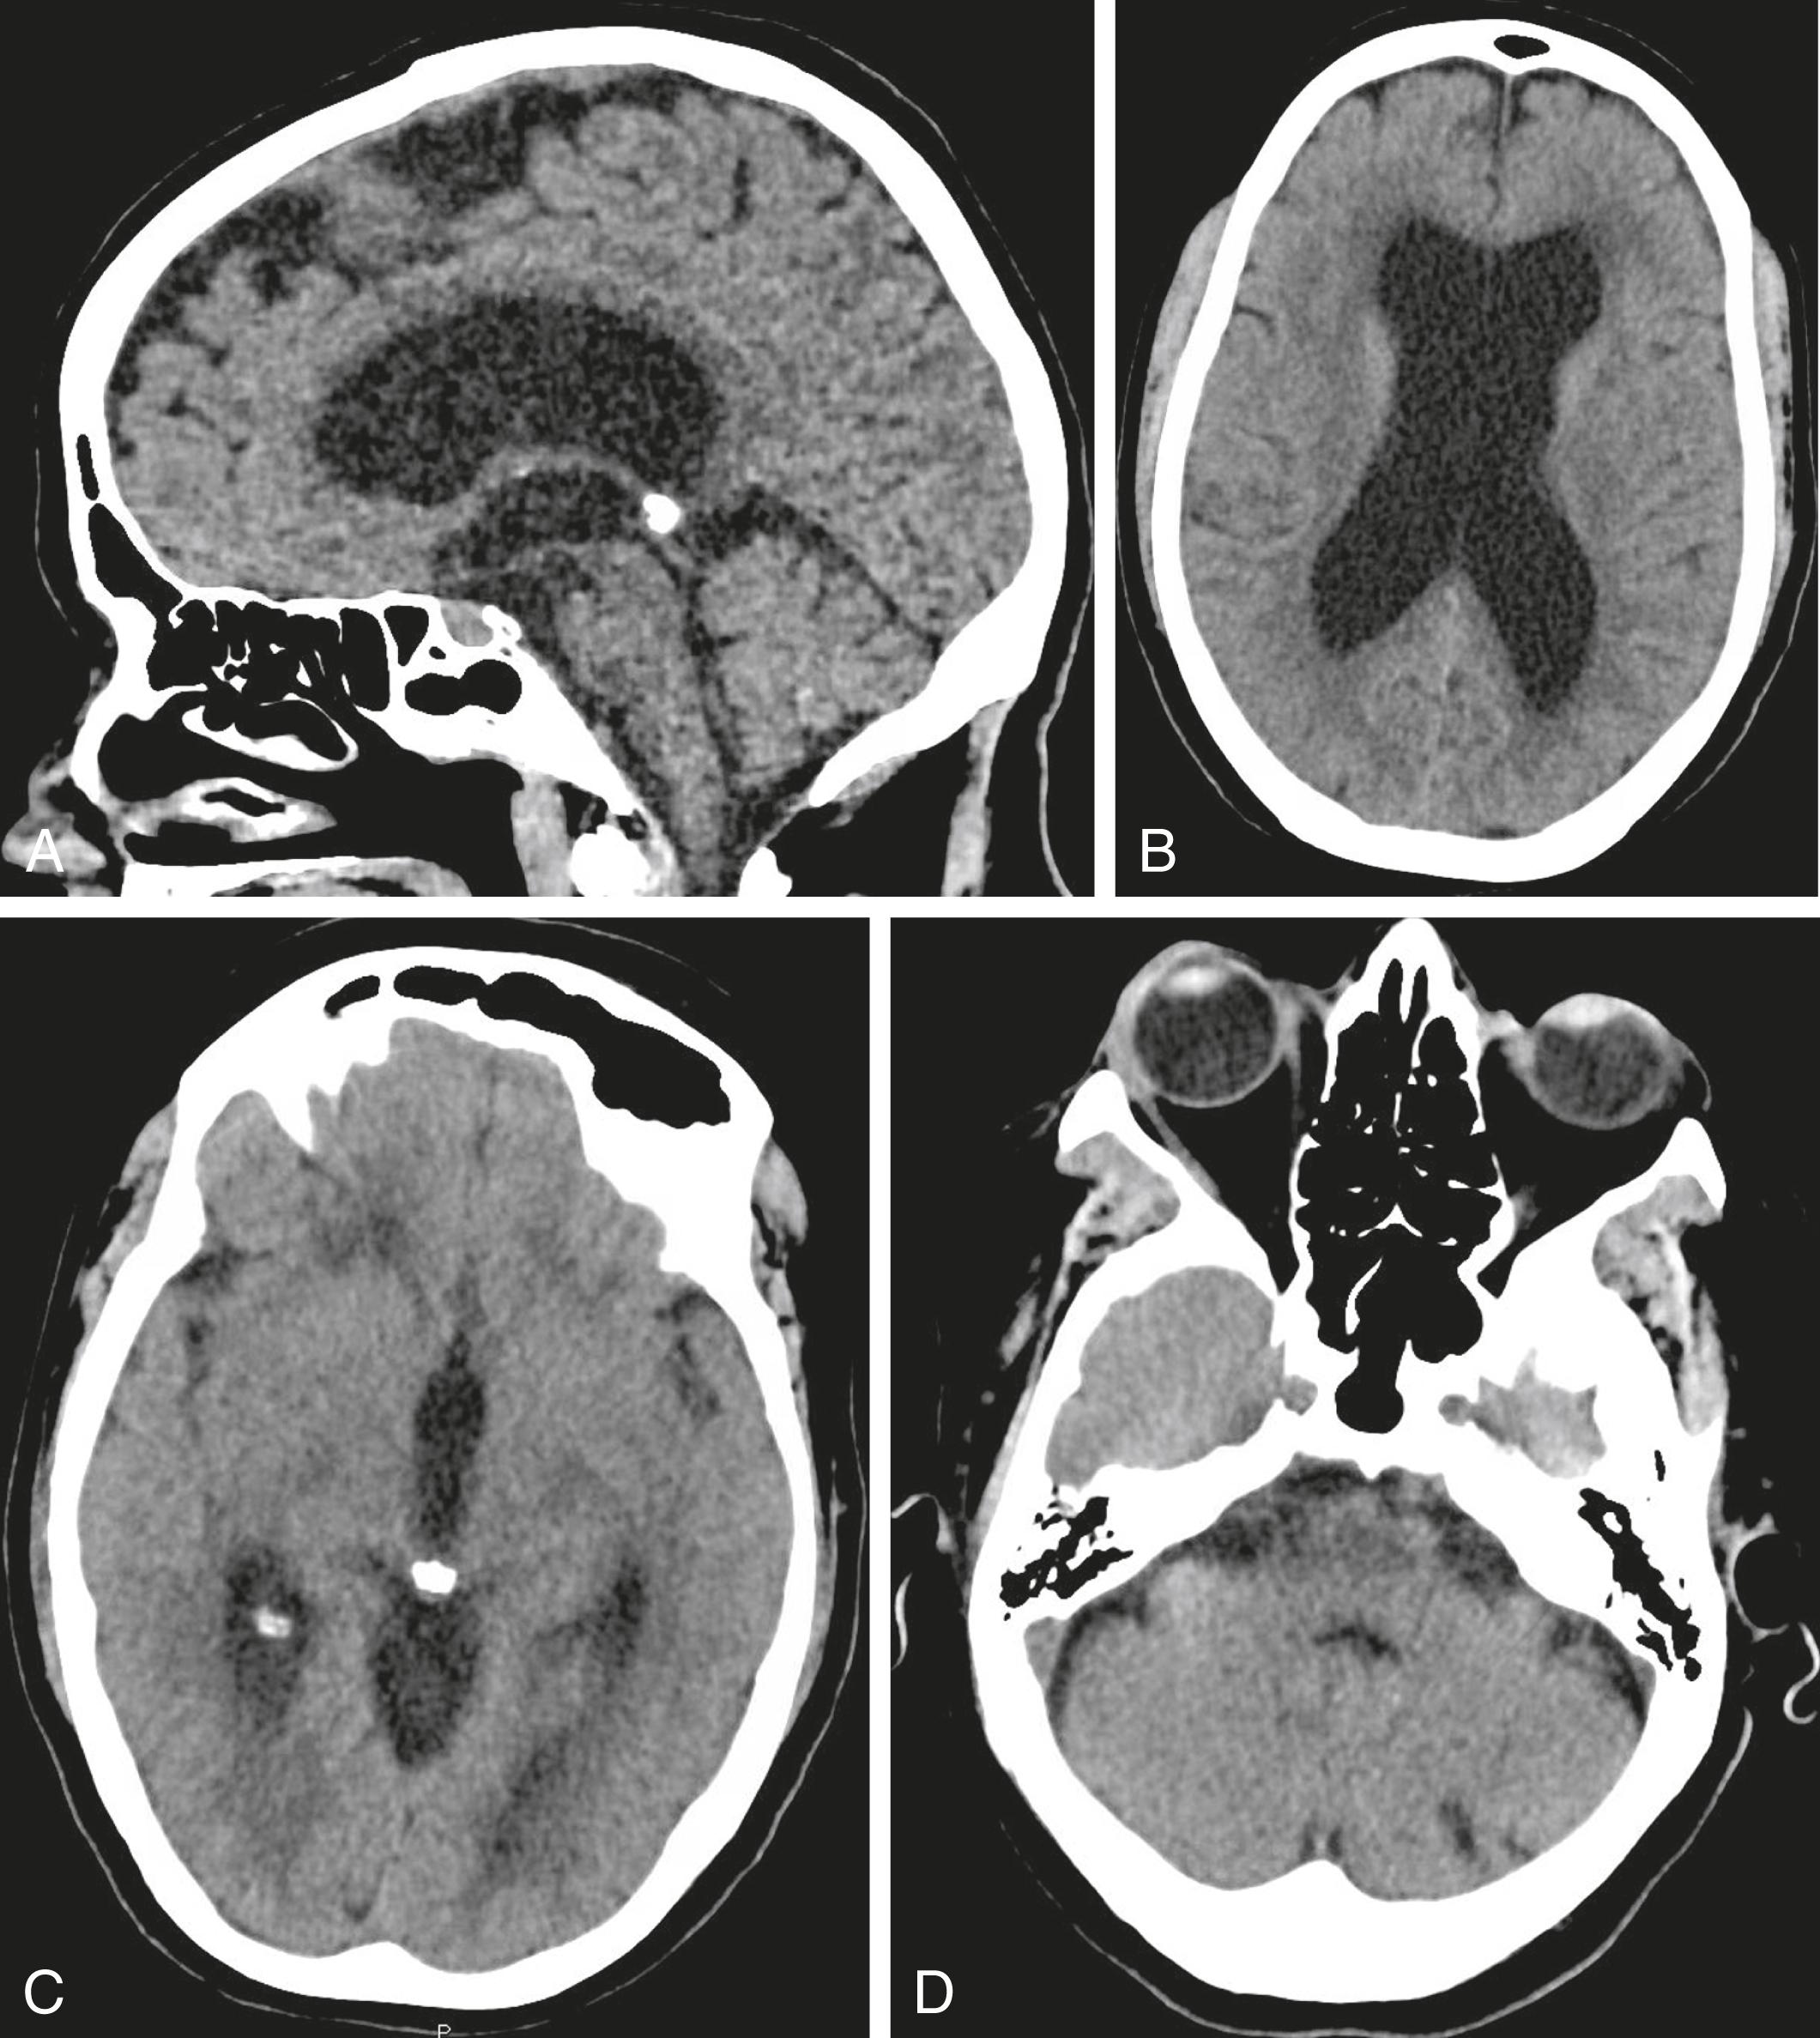

Fig. 63.1, Sagittal (A) and axial (B-D) views of a head CT without contrast demonstrates enlarged lateral (B) and third ventricles (C) with a normal fourth ventricle (D), as well as a hyperdensity near the cerebral aqueduct (C).